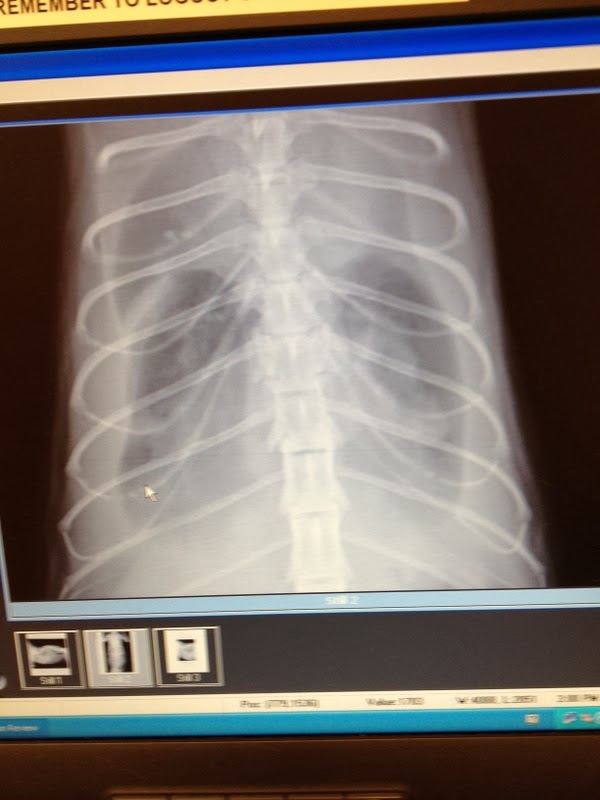

Chest Xray

Those smallest dark areas is only area of breathable space in her lungs.

This afternoon around 2:00EST I noticed Gracie was not breathing normally. Fade to black, this is what started Abby's demise on July 28th last year. So, I was very well aware of the urgent need to seek medical attention when there is abnormal breathing. So I gathered her up and took her to the ER. The Vet that treated her is one of our Vets at the Practice we go to. So he knows me and has treated at least Abby, and I think he saw Jinx too. Anyway I felt a great sense of relief seeing him. From the xrays you can see that Gracie's lungs are very small, that is because there is so much fluid in her chest area. I did not take in every thing he told me except that he does suspect there is cancer. Now, I hope he is wrong, but right now that is the thing that is sticking out in my mind. Gracie is in grave condition right now and needs round the clock attention. They are planning on pulling some of that fluid out of her to give her some relief but also send it out for study to find out what it is. He is supposed to call me later tonight with results of the blood work and let me know who will be taking charge of her care tomorrow. It may be that the same Specialty Vet that has treated both Boo and Abby will also now be looking at Gracie.